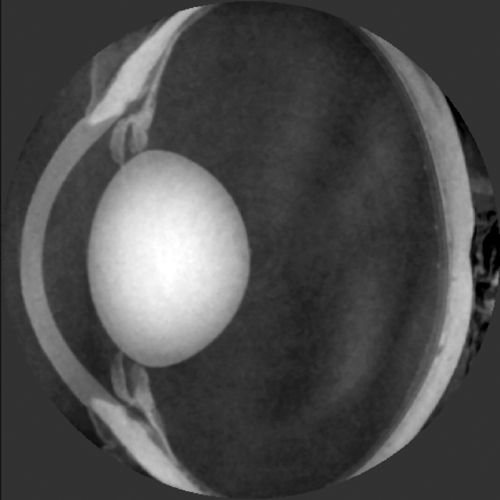

New findings using advanced synchrotron based measurements have allowed detection of very small fluctuations in the refractive index in cortical and nuclear regions of animal [7] and human lenses [8]. The method used is X-ray Talbot interferometry [9-10] and the experiments are conducted at the SPring-8 synchrotron in Japan. The advantage of the technique is that lens refractive index can be measured in any plane, which can produce a three-dimensional map of refractive index, and that measurements can be conducted in the eyeball (Figure 1). In addition, these are the most accurate measurements available.

Figure 1: X-ray Talbot interferometry conducted on a fresh porcine lens.